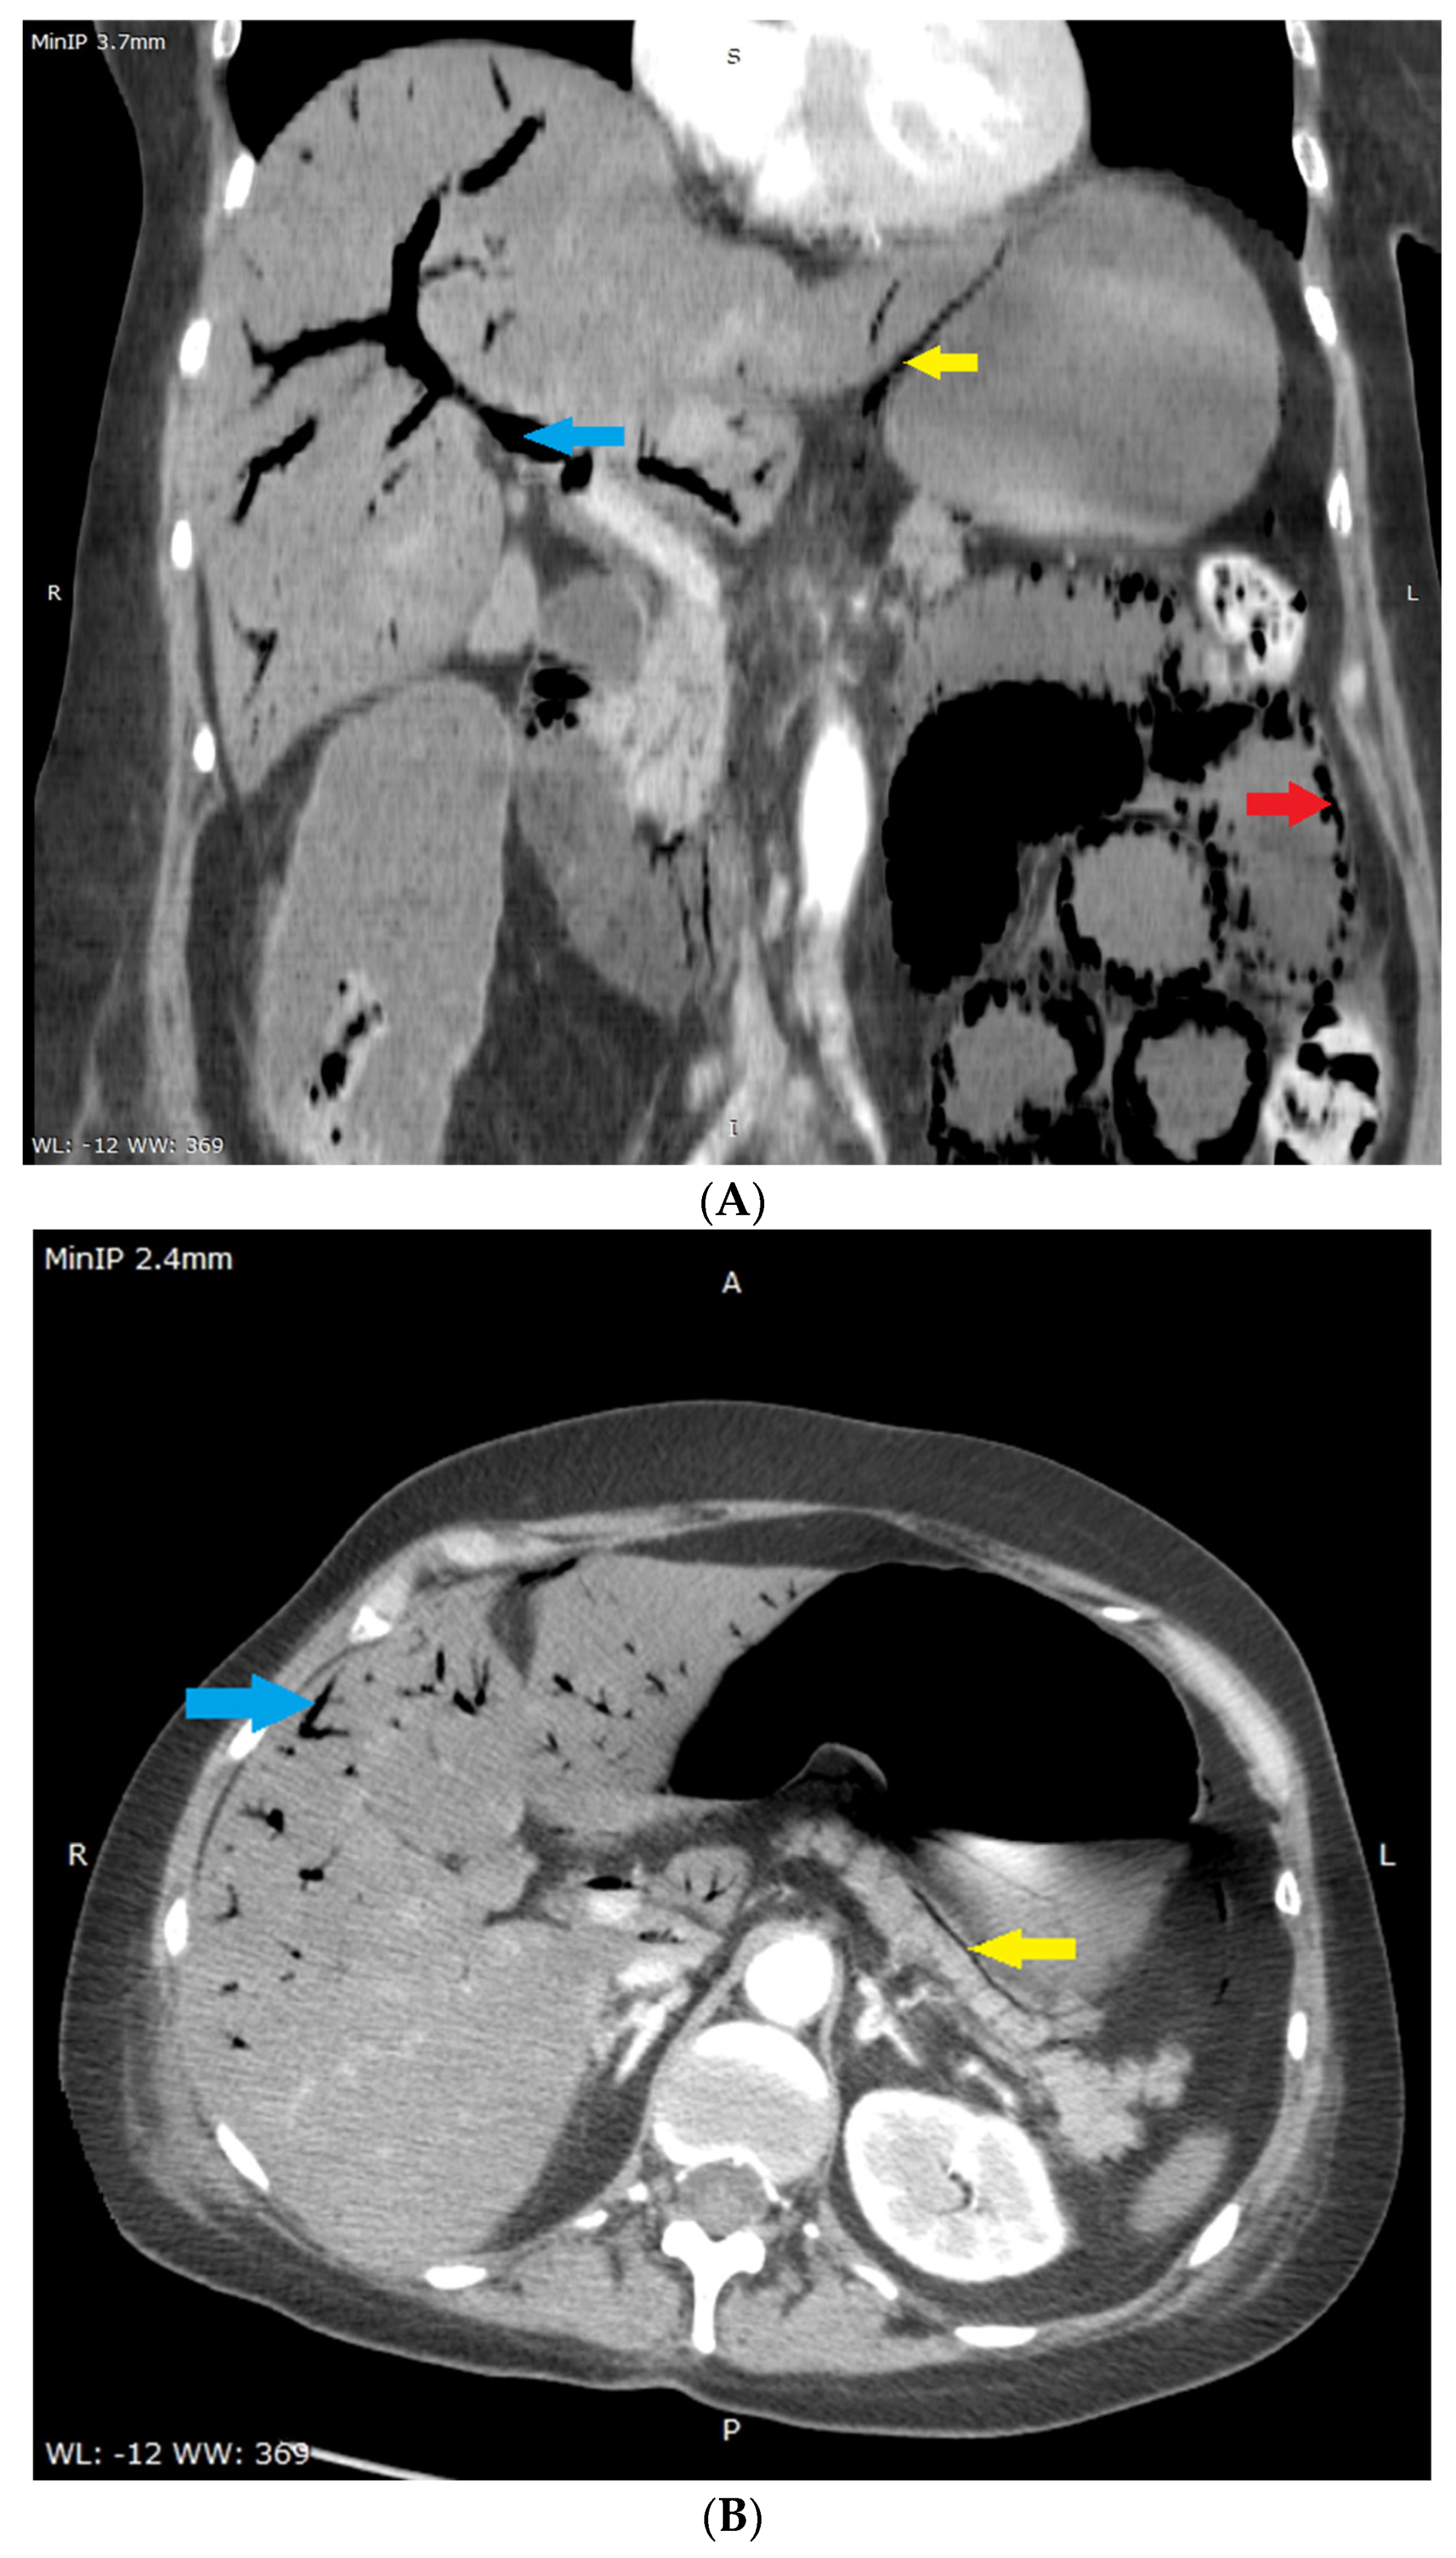

(A,B) Multi-phase abdominal computed tomography performed immediately after liver US. No oral contrast was administered due to urgency–the stomach is filled with accidental content making it isodense to the liver parenchyma. Therefore it is difficult to distinguish this from liver parenchyma in (A). Routine amount of intravenous contrast agent was administered. (A)–coronal reconstruction, portal-venous phase, slice showing the portal vein was selected, minimum intensity projection with 3.7 mm thickness was used in order to better show gas in the portal circulation. Visualized are: gas in the wall of the small intestine (red arrow), gas in the portal vein (blue arrow) and most of its branches-on the picture visible mostly in segments V and VIII, gas in the wall of stomach-lesser curvature (yellow arrow), and distended small intestine filled with fluid (width 33 mm). (B)–axial plane, portal-venous phase, at the level of pancreas, adrenal glands and portal vein, minimum intensity projection with 2.4 mm thickness was used for the same reason as in the (A). Visualized are: gas in the portal vein (visible gas-blood level) and most of its branches (blue arrow), paring of hepatic segment VI portal branches due to anti-gravitational distribution, gas in the wall of stomach (yellow arrow). No gas was present in the hepatic vein circulation as an aquarium sign [7], the celiac trunk and superior mesenteric artery were narrow but patent, there were single gas microbubbles present in the spleen and in superior mesenteric vein, intra- and extrahepatic ducts were not dilated, and no pneumobilia was present.